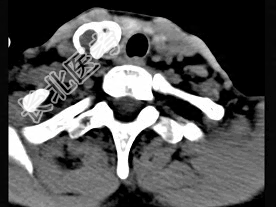

- 多项选择题50岁女性患者,体检发现右侧甲状腺有较硬结节, CT扫描如图所示,请选择正确的描述和答案 ( )

A、右侧甲状腺内见稍低密度影,周边围以环形致密钙化影

B、肿块影与周围结构分界清楚

C、考虑为结节性甲状腺肿

D、考虑为甲状腺癌

E、考虑为甲状腺腺瘤钙化